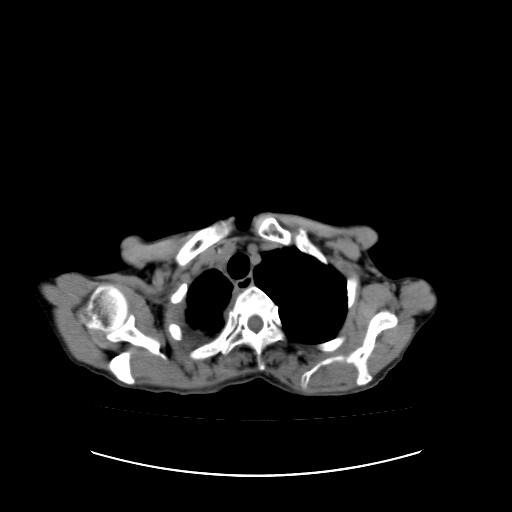

标题: CT16930:女 59 胸痛6个月 胸水脱落细胞学见瘤细胞 [打印本页]

标题: CT16930:女 59 胸痛6个月 胸水脱落细胞学见瘤细胞

右侧胸膜增厚,局部呈结节状增厚,右侧胸腔少量积液。双肺未见确切肿块影。纵隔未见淋巴结肿大。气管、支气管通畅。考虑右侧胸膜间皮瘤(恶性?)可能性大。不除外癌性胸膜炎。

右侧胸廓塌陷,右侧胸膜广泛增厚并见多发胸膜结节,右侧少量胸腔积液并包裹。

右侧广泛胸膜增厚,局部呈结节状增厚,右侧胸腔少量积液。双肺未见确切肿块影。纵隔未见淋巴结肿大。气管、支气管通畅。考虑右侧胸膜间皮瘤(恶性?)可能性大。支持!